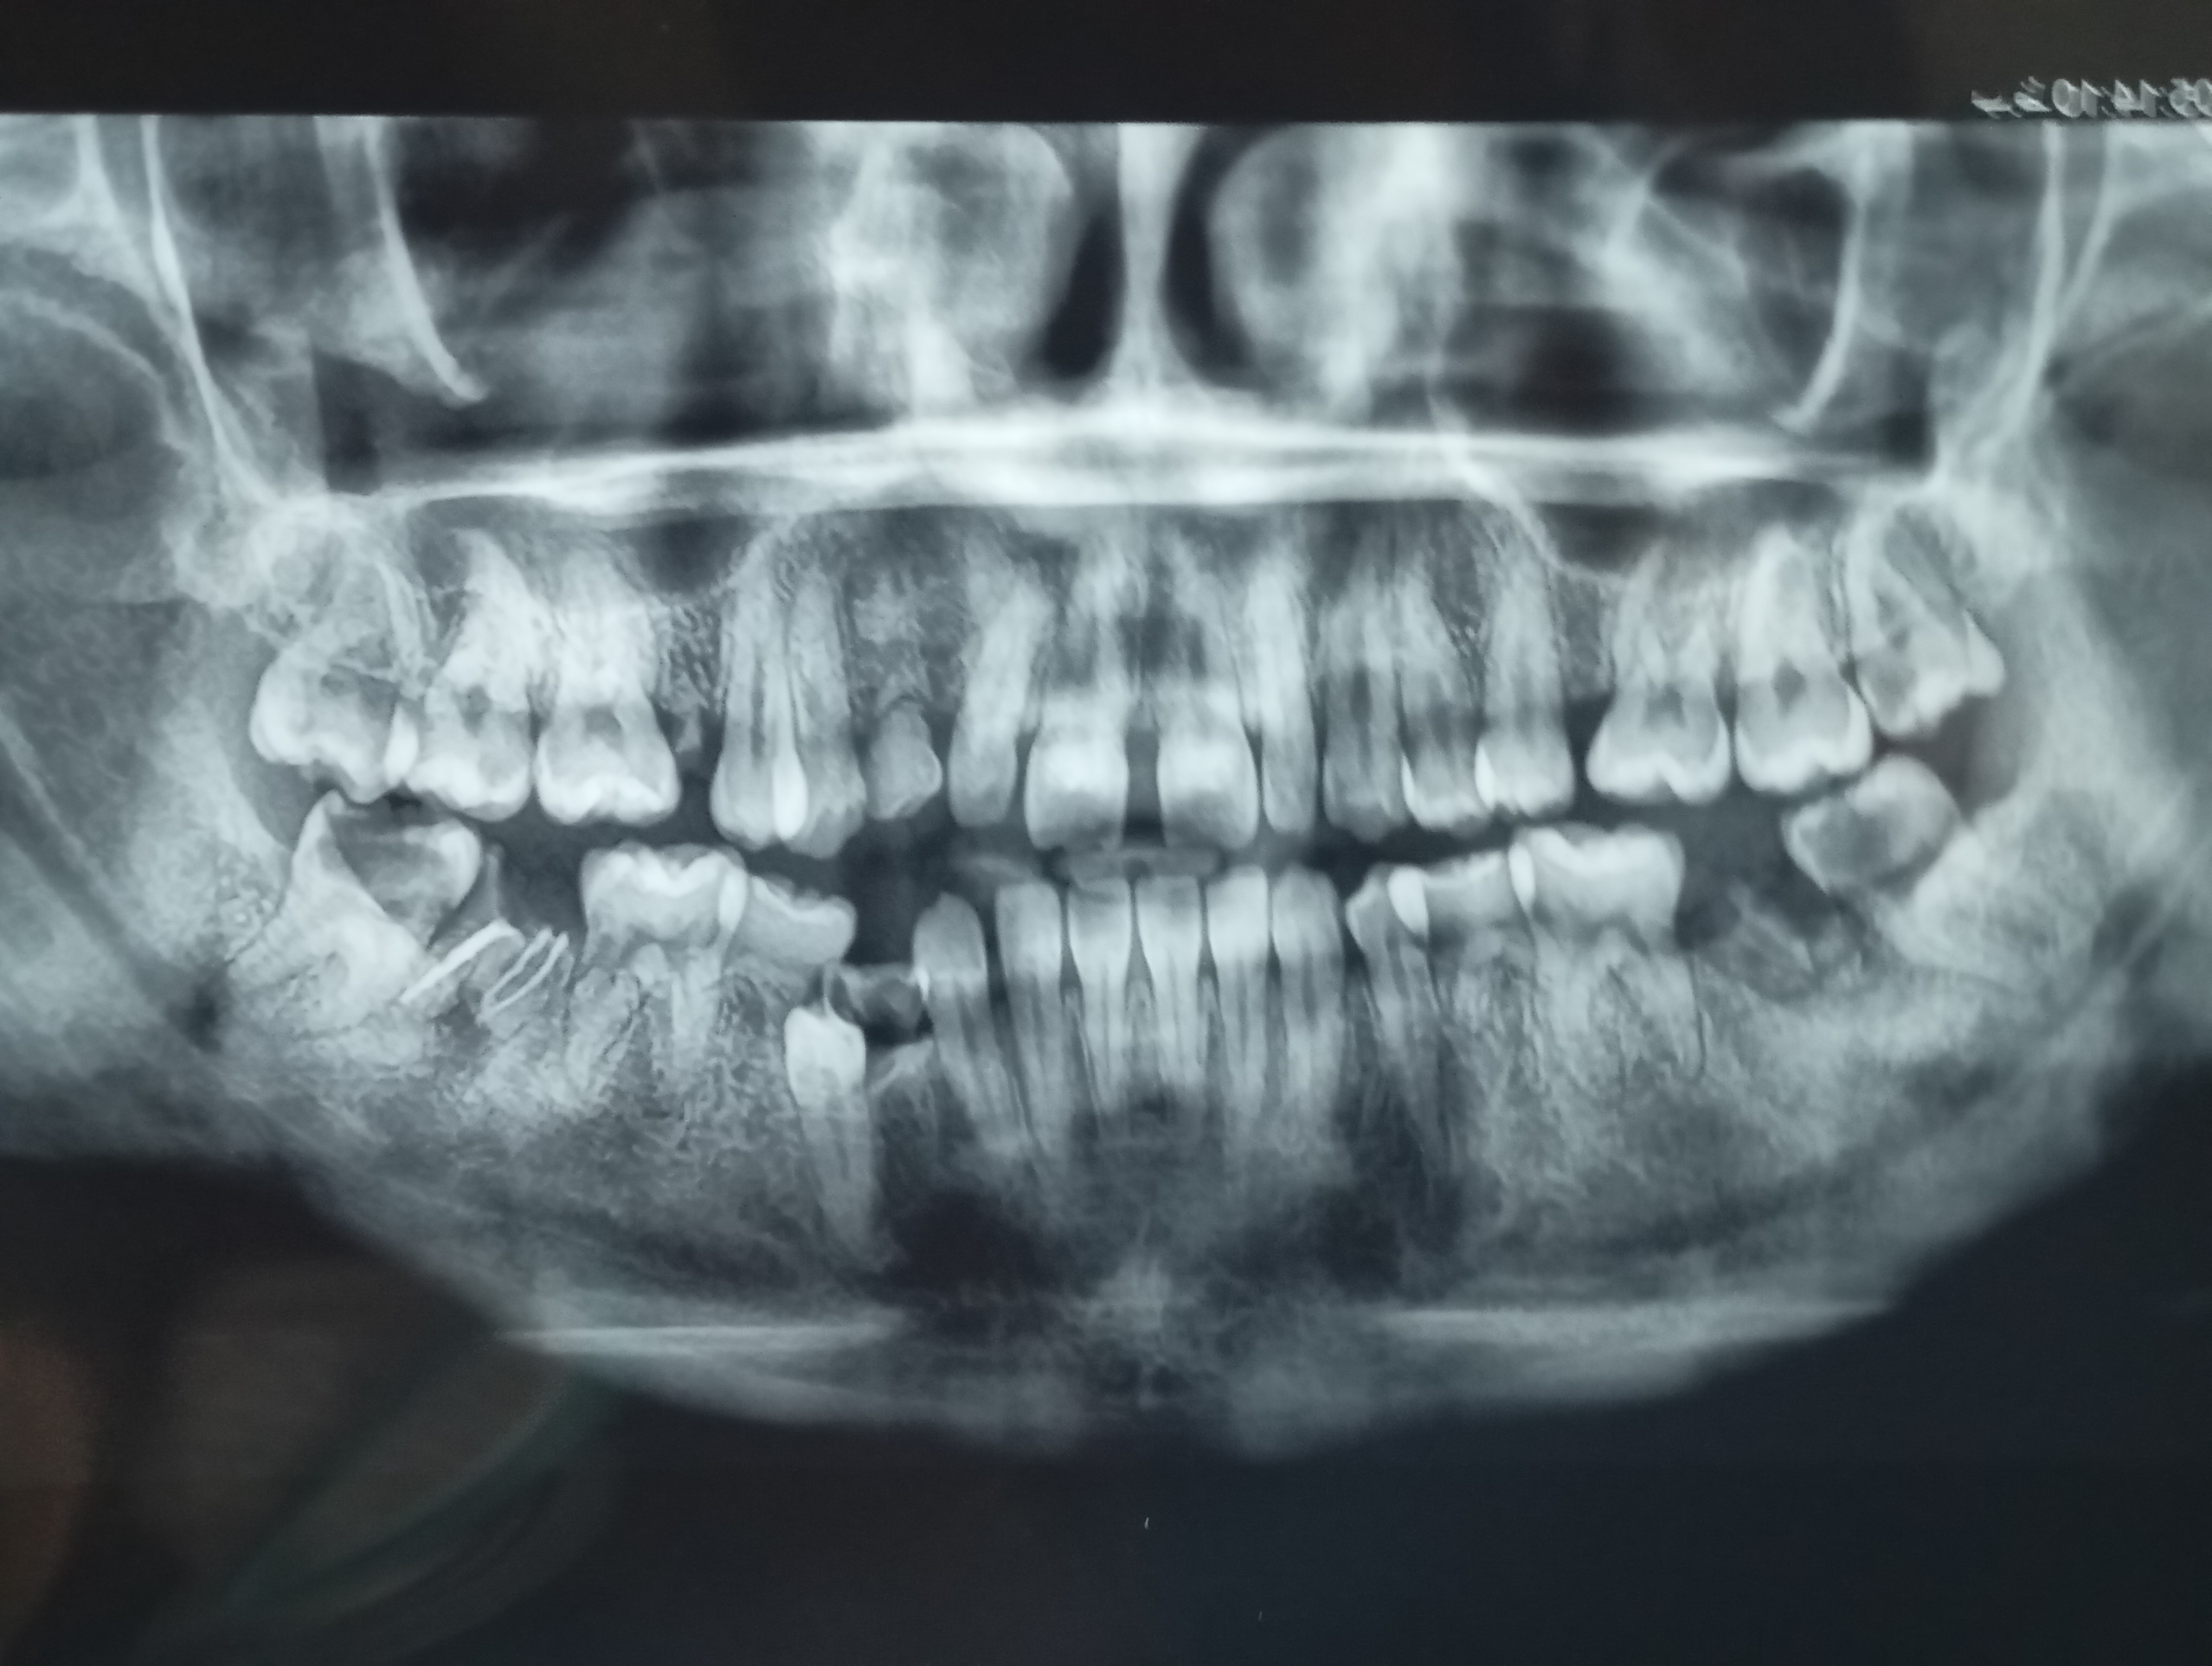

سلام دوستان درد شدید دندون گرفتم رفتم دکتر گفت این دندون خرابه و به عصب نزدیکه نمیتونم بدون جراحی بکشمش (دندون عقل سمت چپ)

چیکارکنم ببینید عکسارو

ببینید دوطرف که علامت زدم دوتا شکسته فقط ریشه مونده دوتایی دندون عقل هم پوکیدن شاید برم جایی دیگه قبول کنه فقط بکشه دندونارو بدون جراحی ولی اون دکتر گفت نه جراحی و من تا یک ماه هزینه جراحی ندارم و درد شدید شدید میگیرم غذا نون و چایی خوردم

یعنی دندون اگه نزدیک به عصب باشه نمیشه بدون جراحی کشیدش؟